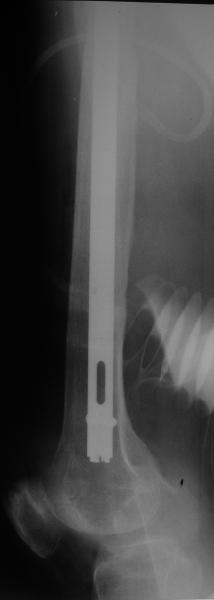

Female, rheumatoid, THA in 2003, car accident in 2006, failed plating. Nailing in Oct 2007. The nail is solid with hollow proximal part where the stem is docked. Last images are in 1 year after

nailing.